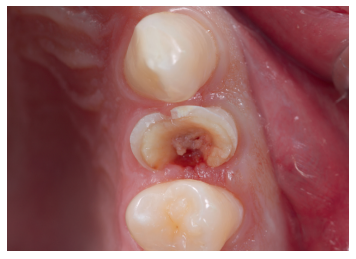

Se presenta en el Máster en Cirugía Oral, Implantología y Periodoncia de la Universidad Alfonso X El Sabio (Madrid, España) un paciente de 24 años derivado para exodoncia del primer premolar superior izquierdo y colocación inmediata de implante debido a una fractura corono-radicular como consecuencia de caries asintomática, con margen distal 2 mm subgingival y limitada estructura remanente (Figuras 1 y 2). Después de un estudio completo del caso, en colaboración con el Máster en Endodoncia de la misma facultad, se planificó la realización de la extrusión quirúrgica, endodoncia y posterior rehabilitación del diente. Dentro de este estudio resultaron de vital importancia las pruebas radiológicas, compuestas por radiografías periapicales y CBCT, que confirmaron la compatibilidad de la anatomía radicular con la realización de una extrusión mínimamente traumática.

con fractura corono-radicular.

fractura corono-radicular.